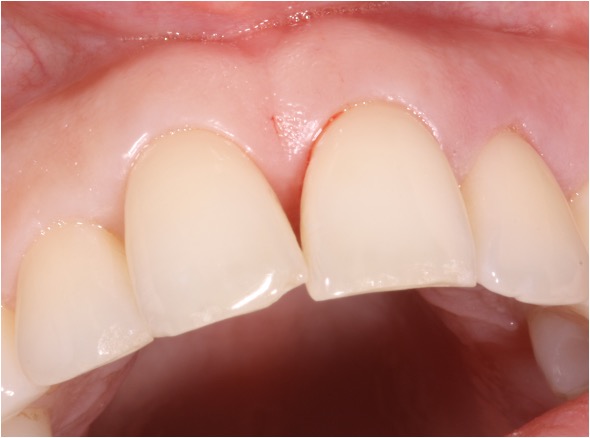

Recession surgery – Free gingival graft

A free gingival graft can cover the recession area and provide “tougher” gum to prevent further recession and make brushing more comfortable. This can also be done around implants. The graft is taken from the roof of the mouth which heals over after a few weeks.